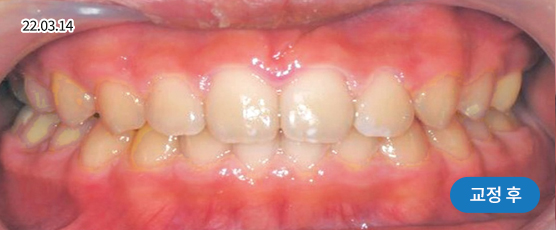

* 본 사진은 동일 조건에서 촬영되었으며, 환자 본인의 동의를 얻어 게재되었습니다.